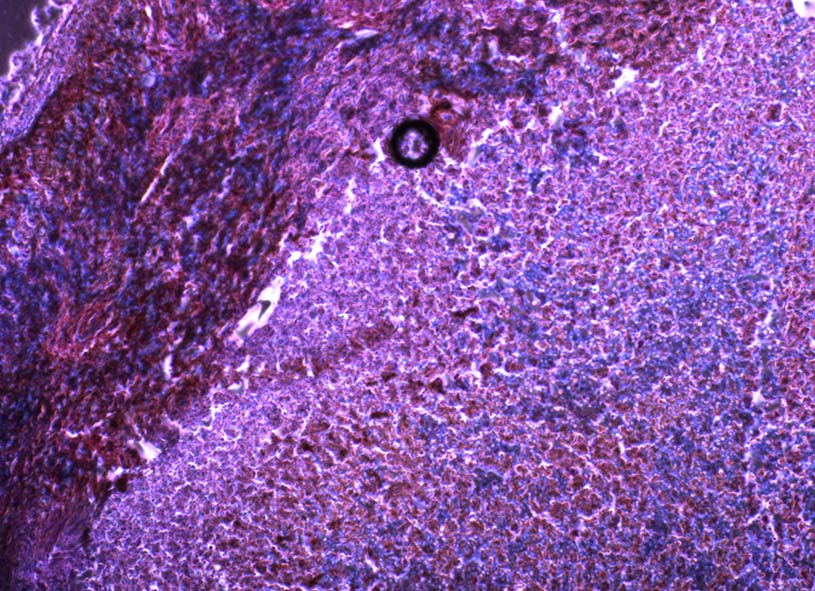

Las regiones de hipoxia en las muestras tumorales se correlacionan con la señalización celular relacionada con la supresión del sistema inmunológico.

Los tumores a menudo crecen tan rápido que no disponen de la sangre suficiente en el tejido, creando un ambiente en el que falta oxígeno (hipoxia). En estas condiciones, las células cancerosas comienzan a autodestruirse, salvo en algunos tipos de cáncer, en los que se ha visto que el microambiente privado de oxígeno que rodea al tumor lo protege frente al sistema inmune.

Esta hipótesis fue confirmada mediante nuevos experimentos. Usando modelos de ratón y muestras de tejido humano, los investigadores encontraron que un ambiente de hipoxia desencadenaba un aumento de los niveles de miR25 y miR93 creando una cascada de señalización celular que finalmente provocó una disminución en los niveles de cGAS. Cuando los investigadores inhibieron miR25 y miR93 en células tumorales, los niveles de cGAS se mantuvieron altos en tumores hipóxicos.